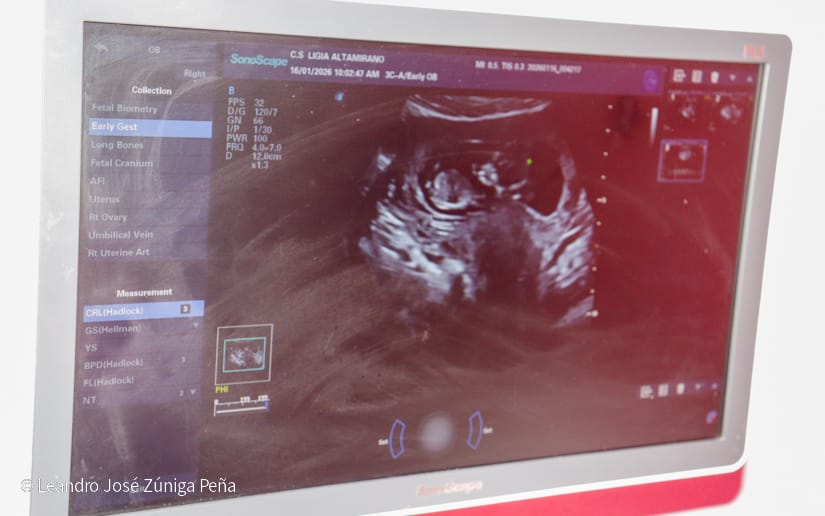

La ginecobstetra y directora del centro, Judith García Aragón, explicó que este tamizaje consiste en la realización de un ultrasonido obstétrico temprano, en donde pueden evidenciar la edad gestacional del bebé, algún tipo de malformación que tenga o un tamizaje para detectar en la madre el desarrollo de preclamsia o de un embarazo pretérmino.

“Estamos cumpliendo el mandato de nuestro Buen Gobierno sobre garantizar la salud, principalmente a la mujer, y especialmente desde el vientre materno, es por eso que el día de hoy estamos atendiendo mujeres embarazadas entre las 11 y 13 semanas de gestación”, expresó.